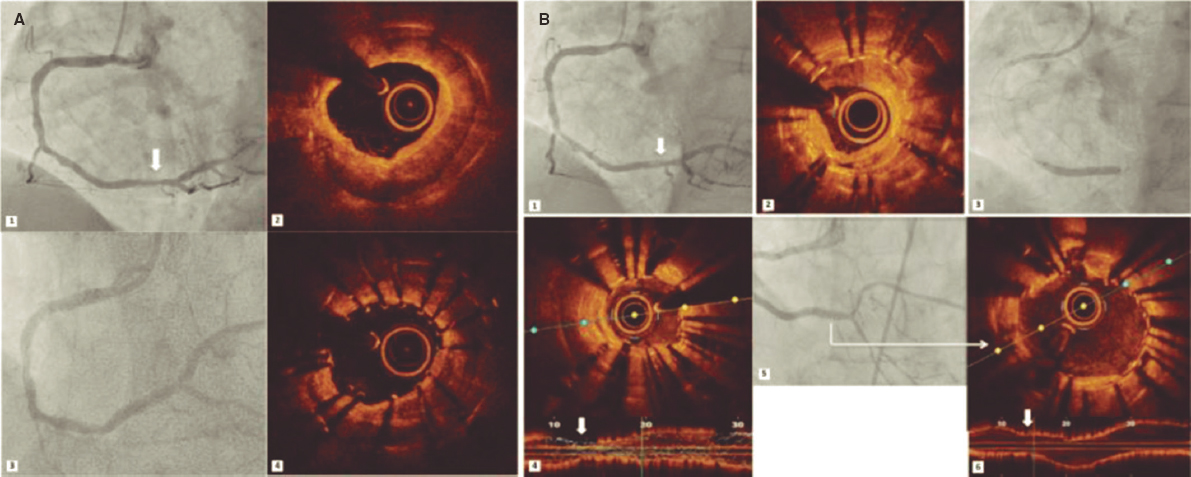

Regarding the procedure, it should be noted that the crossing rate for the ICL balloon was 100% despite a high percentage of plaque preparation was required (62% balloon pre-dilatation, 27% rotational atherectomy). Recently, the combination of rotational atherectomy and ICL has been described as RotaTripsy, suggestive that these 2 calcium debulking techniques may be complementary, since rotational atherectomy facilitates the ICL balloon crossing, and the latter facilitates proper expansion in the presence of circumferential deep calcium plaques.9 The device success rate was 84% (100% in the Disrupt CAD II linical trial) and the clinical success rate was 95% (94% in the Disrupt CAD II trial). And most important of all, no major procedural complications were seen, which is consistent with the Disrupt CAD II trial results. The rupture of the ICL balloon during inflation occurred in 3 cases (12%) without associated complications, yet the rupture of the balloon has been described in a case report resulting in a type C coronary dissection; the interventional cardiologist needs to be aware of this lithotripsy-related potential complication.10 Intravascular imaging were performed in few cases probably because the operator thought it would be difficult to cross an especially severe and calcified lesion with the OCT or IVUS catheter. Consistent with the results of the Disrupt CAD I and II clinical trials and OCT substudy,5,11 it was confirmed that the modification of calcium and the presence of fractures lead to an acute area gain and favorable stent expansion in the lesions assessed through OCT in our series. Figure 1 shows the coronary angiography and OCT of one complex patient treated with ICL; the red arrows seen on figure 1D,E indicate calcium fractures after the ICL.

Figure 1. Intracoronary lithotripsy, angiography, and optical coherence tomography. Patient with severe coronary artery heart disease with severely depressed left ventricular ejection fraction previously treated with coronary artery bypass graft (venous graft-left anterior descending coronary artery, currently occluded). Treatment of left main coronary artery, left anterior descending artery, and diagonal branches. A: pre-intracoronary lithotripsy angiography. B: Impella-assisted PCI of left anterior descending coronary artery. Arrow indicates inflated lithotripsy balloon. C: successful final angiographic result after stenting. D, E and F: optical coherence tomography cross-sectional images of a post-lithotripsy calcified lesion. Red arrows indicate calcium microfractures after intracoronary lithotripsy.